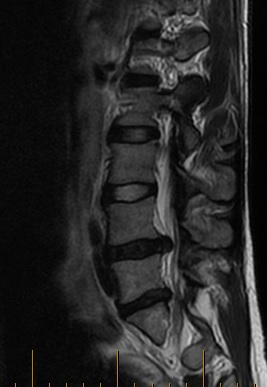

lumbar MRI

Here’s the whinge: Somehow I have a “bulging disk” in my back pushing on a nerve, causing pain from my hip to my toes. See that black thing between the vertebrae? It’s supposed to be a tidy little balloon staying neatly between the bones, not a jelly-filled donut with the jelly squeezed out.